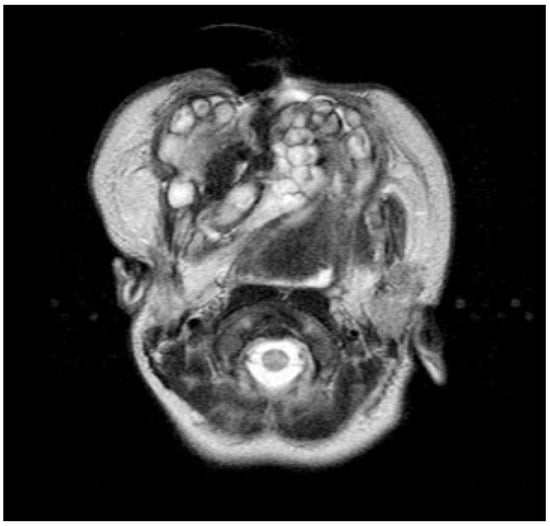

Neonatal examination exhibited frontonasal dysmorphism (bifid anterior cranium, hypertelorism, blepharophimosis, broad nasal bridge, and broad nasal tip), low implantation of the ears, a short neck, bifid and protrusive tongue covered with lanugo, inferior lip and buccolabial sulci malformation, macrostomia, microretrognathia, and except for a small slit in the lateral regions, through which only the end of alveolar ridge could be seen, the mandible and maxilla were fused at gum level (Figure 2). Nasoendoscopy showed complete cleft of the median palate. Magnetic resonance imaging (MRI) revealed orbital hypertelorism, midline cranial cleft ending just superior to the nasal dorsum, agenesis of the corpus callosum, and maxillomandibular fusion (Figure 3 and Figure 4).

Figure 3.

Coronal view on magnetic resonance imaging confirms the midline cranial cleft.

Figure 4.

Magnetic resonance image showing the maxillomandibular bony fusion.